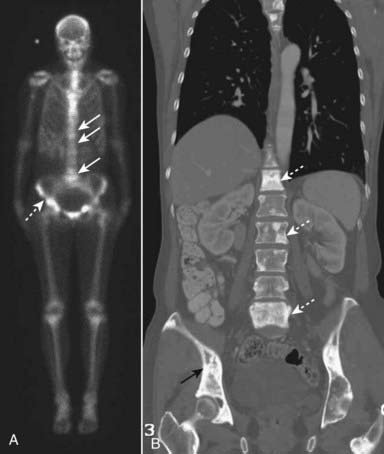

imageThe current screening study of choice for the detection of spinal metastases is a Technetium-99m (Tc 99m) bone scintiscan (radionuclide bone scan). The technetium is most commonly bound to methylene diphosphonate (MDP) that transports the Tc 99m to bone. A radionuclide bone scan is relatively inexpensive, widely available, and screens the entire body. While bone scans are highly sensitive to the presence of metastatic deposits, they are not very specific. In many cases, a confirmatory study, usually a conventional radiograph, is needed to exclude other causes of abnormal radiotracer uptake such as fractures, infection, and arthritis (Fig. 24-15).

image

Figure 24-15 Metastases, radionuclide bone scan, and CT.

A, A Technetium-99m methylene diphosphonate (MDP) bone scan demonstrates abnormal tracer uptake in numerous areas including the spine (solid white arrows) and pelvis (dashed white arrow). Because of the nonspecific nature of positive bone scans, a confirmatory study, usually conventional radiography, is obtained as well. B, In this case the patient had undergone a CT scan and the coronal reformatted image shows numerous osteoblastic lesions in the spine (dotted white arrows) and the pelvis (solid black arrow) corresponding to the lesions seen on bone scan. This patient had known breast carcinoma.